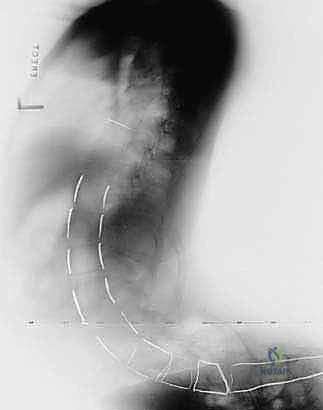

FIG 3 • The sacral ala clearly demonstrated during a myelokyphectomy with only the surgeon’s finger inserted anterior to the ala. This illustrates safe anterior palpation for assessment, not dissection.